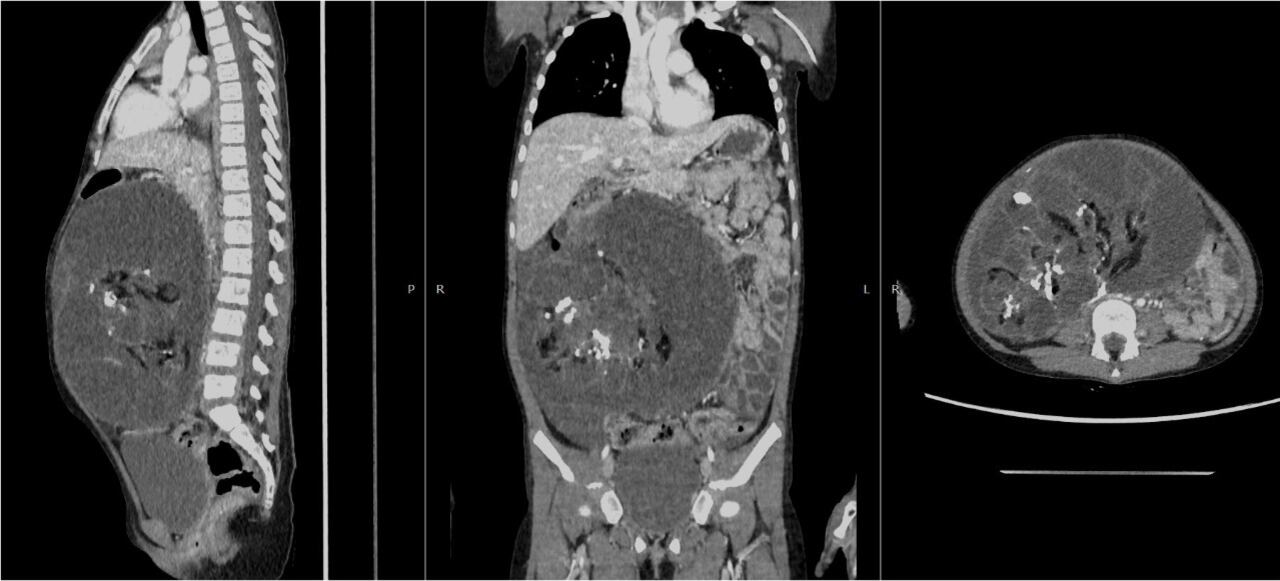

“El tumor ocupaba parte de su abdomen y se estaba desplazando a otros órganos que impedían su normal funcionamiento”, detalló Soledad entre lágrimas al recordar el estado en el que se encontraba su pequeña.

La menor fue atendida primero en el hospital EsSalud de Pucallpa, donde se le realizó algunos exámenes que determinaron que se trataba de un tumor ovárico que iba creciendo; sin embargo, por la complejidad del caso derivaron a la pequeña paciente al hospital Rebagliati de Lima.